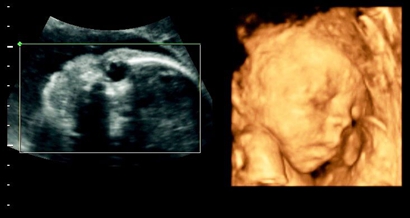

四维彩超男孩翻盘实例,为什么四维是男孩结果生女孩?

网上流传着很多宝妈做四维彩超检查,医生说是男孩,但是结果生出来是女孩的案例,那么四维彩超男孩翻盘实例有哪些,为什么四维是男孩结果生女孩?四维彩超男孩翻盘实例:有..

四维女孩却生了男孩,四维女孩翻盘几率大吗?

四维彩超是目前比较流行的孕检之一,四维能对胎儿头面部立体成像,可清晰显示胎儿的状态,网上很多四维是女孩但是却生了男孩的案例,那么四维女孩翻盘几率大吗?四维女孩却..

四维彩超哪些数值可以判断男女?也会翻盘吗?

在我们的生活中普通的b超检查生男生女,四维彩超检查生男生女,还有的用nt检查看生男生女以及唐氏筛检查生男生女等等,在如此众多的方法中,四维彩超最受欢迎,因为四维彩..

b超单看男女有诀窍附图片!6个数据看懂不翻盘踩坑

很多宝妈在孕期的时候都比较无聊,因此猜测肚子里宝宝的性别成为了很多宝妈在孕期的“娱乐活动”,民间判断胎儿是男是女的方法千奇百怪,但是准确度都不高,我们都知道b超..